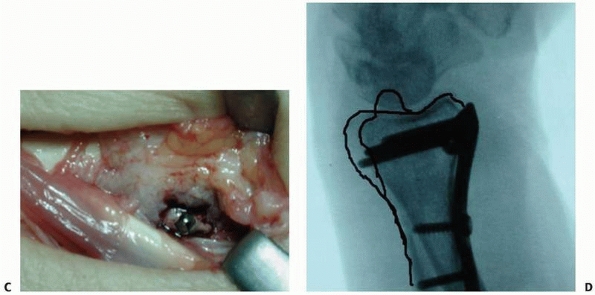

palmar buttress, across which tension can be applied (Fig. 30-25).

![]() |

FIGURE 30-25 A. Typical three-part intra-articular fracture of the distal radius. B. Depression of the lunate facet palmarly is difficult to reduce by closed methods. C. A plate applied palmarly to the lunate facet reduces and mortars both the DRUJ and the radiocarpal joint.